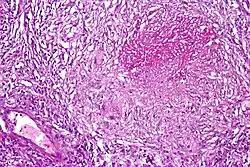

Pulmonary tuberculosis characterized by granulomatous inflammation with necrotizing epithelioid granulomas. Low power view. H&E stain. -

Pulmonary tuberculosis featuring necrotizing granulomas, H&E stain. -

Pulmonary tuberculosis featuring necrotizing granulomas, high power view, H&E stain. -